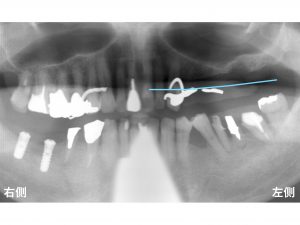

以下は初診時です。

下顎右側の奥歯と上顎左側の奥歯が欠損しています。

下顎の右側は2歯が欠損しています。

上顎の左側の奥歯もグラグラしています。

この歯は抜歯が必要な状態です。

もともとの骨の位置を青線 で表記します。

現在の骨の位置は、

以下の赤線 です。

以下の赤色の領域 が骨が吸収した範囲です。

かなりの骨吸収があります。

他にも問題があったのが、

上顎洞 です。

上顎洞 とは、

上顎の奥歯の上方にある空洞のことです。

この空洞があるため、上顎の奥歯では、

インプラントを埋め込むための高さに制限があるのです。

以下の緑色の領域 は、空洞です。

骨吸収があるため、

どうしてもインプラントを埋め込むには問題が大きいのです。

骨の高さには制限がでてしまいます。